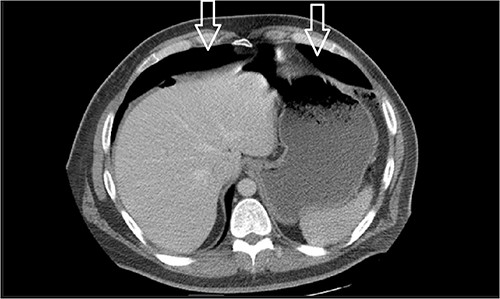

Eleven days post-discharge, he presented to the ER with the same symptoms. CT once again demonstrated pneumoperitoneum (see Fig. 3). Perforated hollow viscus structure is suspected; however, no rim-enhancing abscess is evident. Given his previous two negative ex-laps, a repeat EL was deferred. A conservative treatment plan of pneumoperitoneum was implemented for IP.

Amount of pneumoperitoneum increased compared with previous CTs.